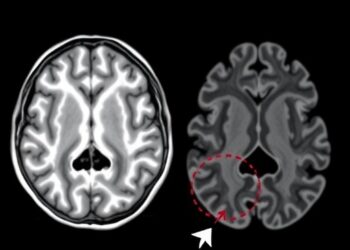

MRI Reveals Hippocampal Changes in Low-Birth-Weight Infants